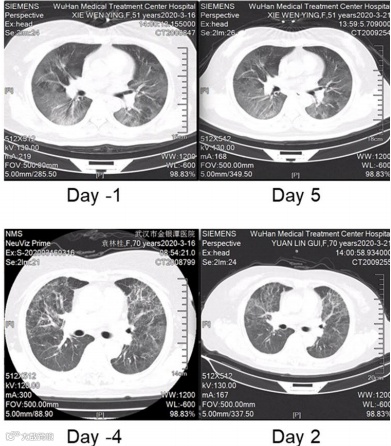

上海复旦大学华东医院及上海交通大学医学院瑞金医院等联合发表了一篇关于外泌体雾化吸入文章安全性及有效性的研究,对感染COVID-19的7名患者通过气溶胶吸入人脂肪来源的MSC (haMSC-Exos)外泌体进行治疗(图4)。7名重症COVID-19 相关肺炎患者(4名男性和3名女性)每日吸入haMSCs-Exos(2.0 × 108纳米囊泡),并保持连续5天的持续治疗。所有感染COVID-19 患者对haMSC-Exos雾化吸入的耐受性良好,雾化期间无不良事件或临床相关问题出现。7例患者中有4例肺部病变的消退明显,肺部CT成像显示双肺病变在治疗前后对比得到不同程度的改善。

图4 COVID-19患者吸入haMSC-Exos前后胸部CT扫描的变化